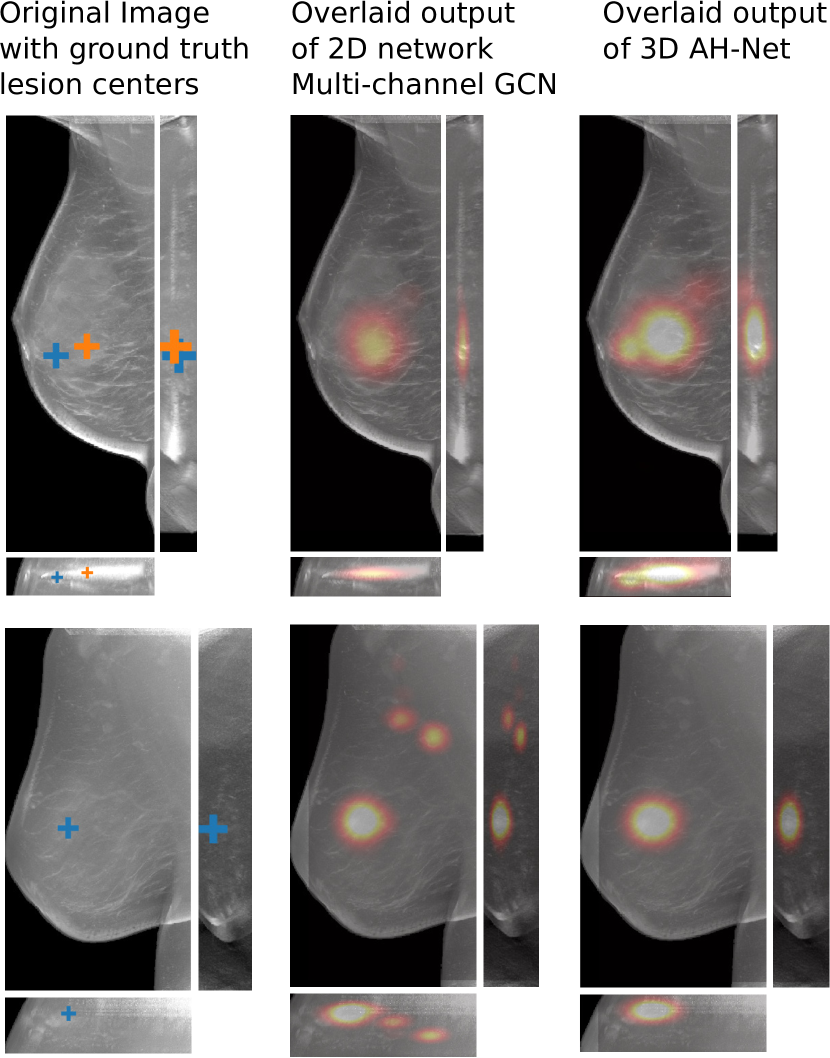

Refer to caption

Figure 5: The visual comparisons of the network responses on 2 different DBT volumes from 2D GCN and the 3D AH-Net with the encoder weights transferred from it. Each volume is visualized with the maximum intensity projection of the xy𝑥𝑦xy plane (top-left), the xz𝑥𝑧xz plane (bottom) and the yz𝑦𝑧yz plane (right). The ground truth lesion centres are shown on the left. With the additional AH-Net Decoders, 3D AH-Net could effectively detect the missing lesion in the first volume (upper row) and remove the false positives in the second volume (lower row).

Non-maximal suppression is performed on the network output map to obtain the lesion locations. The network responses at the local maximal voxels are considered as the confidence scores of the cancerous findings. Fig. 5 shows some visual comparison of the networks output.